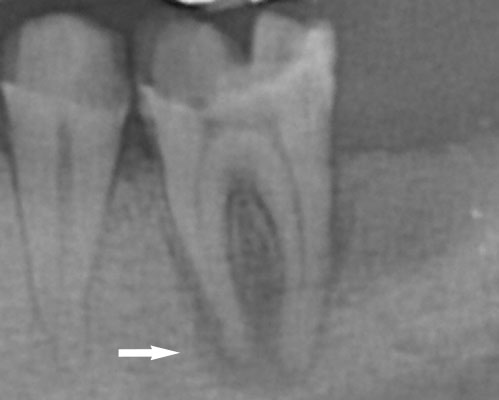

歯周病の特徴 初期症状として、歯ぐきからの「出血」があります。歯磨きの時に歯磨き剤や歯ブラシが赤く染まっていて気づくことが多いようです。病状が進行すると、腫れや痛みが出てきます。歯ぐきの違和感として感じることもあります。ただ、汚れが原因の歯周病の場合、痛みや腫れが起きるのには波があり、症状が出ても2~3日で治ってしまうのが特徴です。レントゲンではアリ地獄のように斜めに骨が溶けていきます。